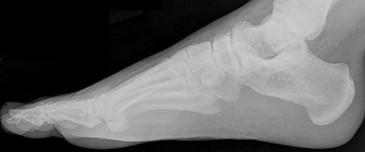

Figures 9a and 9b are the radiographs of a 19-year-old woman with a painful juvenile bunion. The pathologic findings associated with this deformity

include a

The radiographs show a hallux valgus deformity with a laterally deviated distal metatarsal articular surface, a large intermetatarsal angle with medial deviation at the first metatarsocuneiform joint, an elongated medial collateral ligament, and a contracted lateral collateral ligament. There is no distal 1-2 transverse intermetatarsal ligament. The distal transverse ligament in the first interspace extends from the second metatarsal to the lateral (fibular) sesamoid, remains intact, and keeps the sesamoids in a lateral position as the first metatarsal head migrates medially.